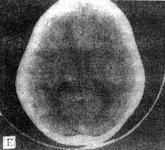

球形細胞腦白質營養不良即球形細胞型白質營養不良(globoid cell leukodystrophy,GLD),又名Krabbe白質營養不良癥、Krabbe病、Krabbe急性嬰兒型腦硬化、球形白細胞發育障礙癥、先天性全身肌發育不全、類球狀細胞型白質腦病、類球狀細胞型彌漫性硬化癥、Krabbe綜合征等。為常染色體隱性遺傳,是β-半乳糖苷酶的缺乏或其活性減低所致腦脂質沉積病。